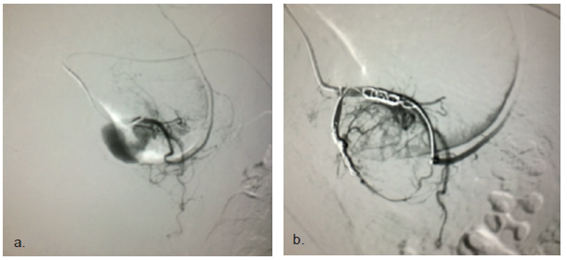

La arteria más frecuentemente comprometida fue la gastroduodenal (figura 1) en cinco casos. La rama ascendente de la arteria cólica derecha, la rama ascendente de la arteria cólica izquierda y la arteria esplénica, estuvieron comprometidas, cada una, en un caso (figura 2).

Figura 1. Hemorragia digestiva alta. a) Hemorragia proveniente de la arteria gastroduodenal. b) Control después de la formación de émbolos con microespirales y micropartículas.